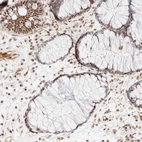

Immunohistochemical staining of human pancreas shows strong nuclear positivity in exocrine glandular cells.